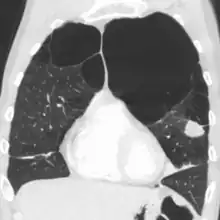

A chest X-ray and complete blood count may be useful to exclude other conditions at the time of diagnosis.[80] Characteristic signs on X-ray are hyperinflated lungs, a flattened diaphragm, increased retrosternal airspace, and bullae, while it can help exclude other lung diseases, such as pneumonia, pulmonary edema, or a pneumothorax.[81] A high-resolution CT scan of the chest may show the distribution of emphysema throughout the lungs and can also be useful to exclude other lung diseases.[23] Unless surgery is planned, however, this rarely affects management.[23] A saber-sheath trachea deformity may also be present.[82] An analysis of arterial blood is used to determine the need for oxygen; this is recommended in those with an FEV1 less than 35% predicted, those with a peripheral oxygen saturation less than 92%, and those with symptoms of congestive heart failure.[22] In areas of the world where alpha-1 antitrypsin deficiency is common, people with COPD (particularly those below the age of 45 and with emphysema affecting the lower parts of the lungs) should be considered for testing.[22]

Axial CT image of the lung of a person with end-stage bullous emphysema